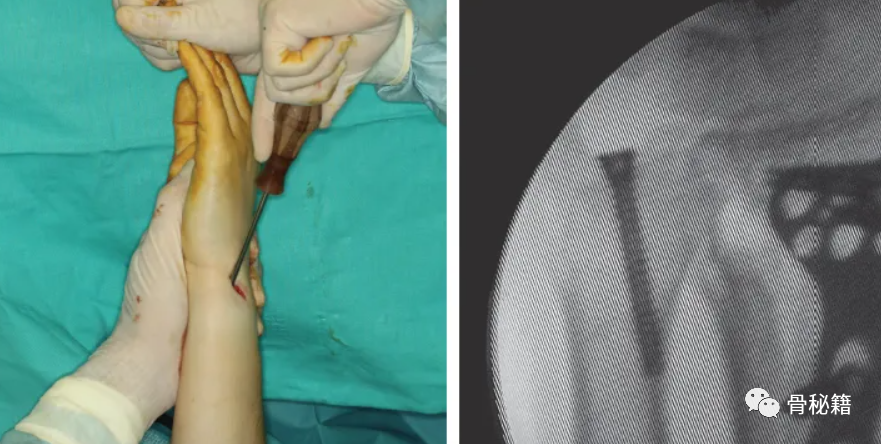

采用茎突入路进行手术复位与固定,拧入空心螺钉

固定后 术中用探钩检查TFCC稳定性,发现固定后稳定性较好

通过一个 1.5 到 2 厘米的切口,从茎突底部的背侧近端到掌侧远端切开,注意不要损伤尺神经,保持尽量旋后的状态,也可通过该入路重建TFCC